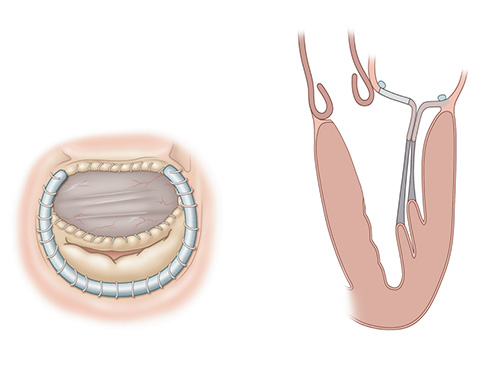

Robotic septal myectomy with anterior leaflet patch. (A) postoperative heart — superior view (B) postoperative heart — long axis view

Mitral valve abnormalities are a key feature of hypertrophic obstructive cardiomyopathy. Early in systole, the anterior leaflet of the mitral valve is one-half of the LVOT. In the robotic approach, surgeons insert a patch that essentially works as an LVOT enlargement maneuver by moving the anterior leaflet into a horizontal position early in systole and away from the septum.

The endoscopic robotic septal myectomy with large patch augmentation of the anterior mitral valve leaflet is a radical change in paradigm. Preliminary results of this novel approach are promising. In a review of 26 patients with a mean septal thickness of 22.3+5.3cm, all patients had systolic anterior motion and mean LVOT gradient 128.2+38.99mmHG. There were no deaths postoperatively, no systolic anterior motion in any patients, and the mean LVOT gradient was in single digits.

While the standard surgical septal myectomy is performed via sternotomy, NewYork-Presbyterian/Weill Cornell offers a totally endoscopic robotic procedure that allows for both septal myectomy and augmentation of the anterior leaflet. The many potential advantages to this minimally invasive approach include exquisite visualization of the septum from the aortic valve to the apex of the heart. The endoscopic robotic approach also allows for easier access to mitral valve subchordal structures and the avoidance of residual postoperative gradients due to inadequate myectomy by enlarging both sides of the left ventricular outflow tract (LVOT).